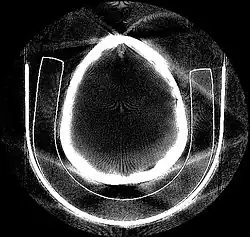

Resulting tomographic image from a plastic skull phantom. Projected X-rays are clearly visible on this slice taken with a CT-scan as image artifacts, due to limited amount of projection slices over angles.